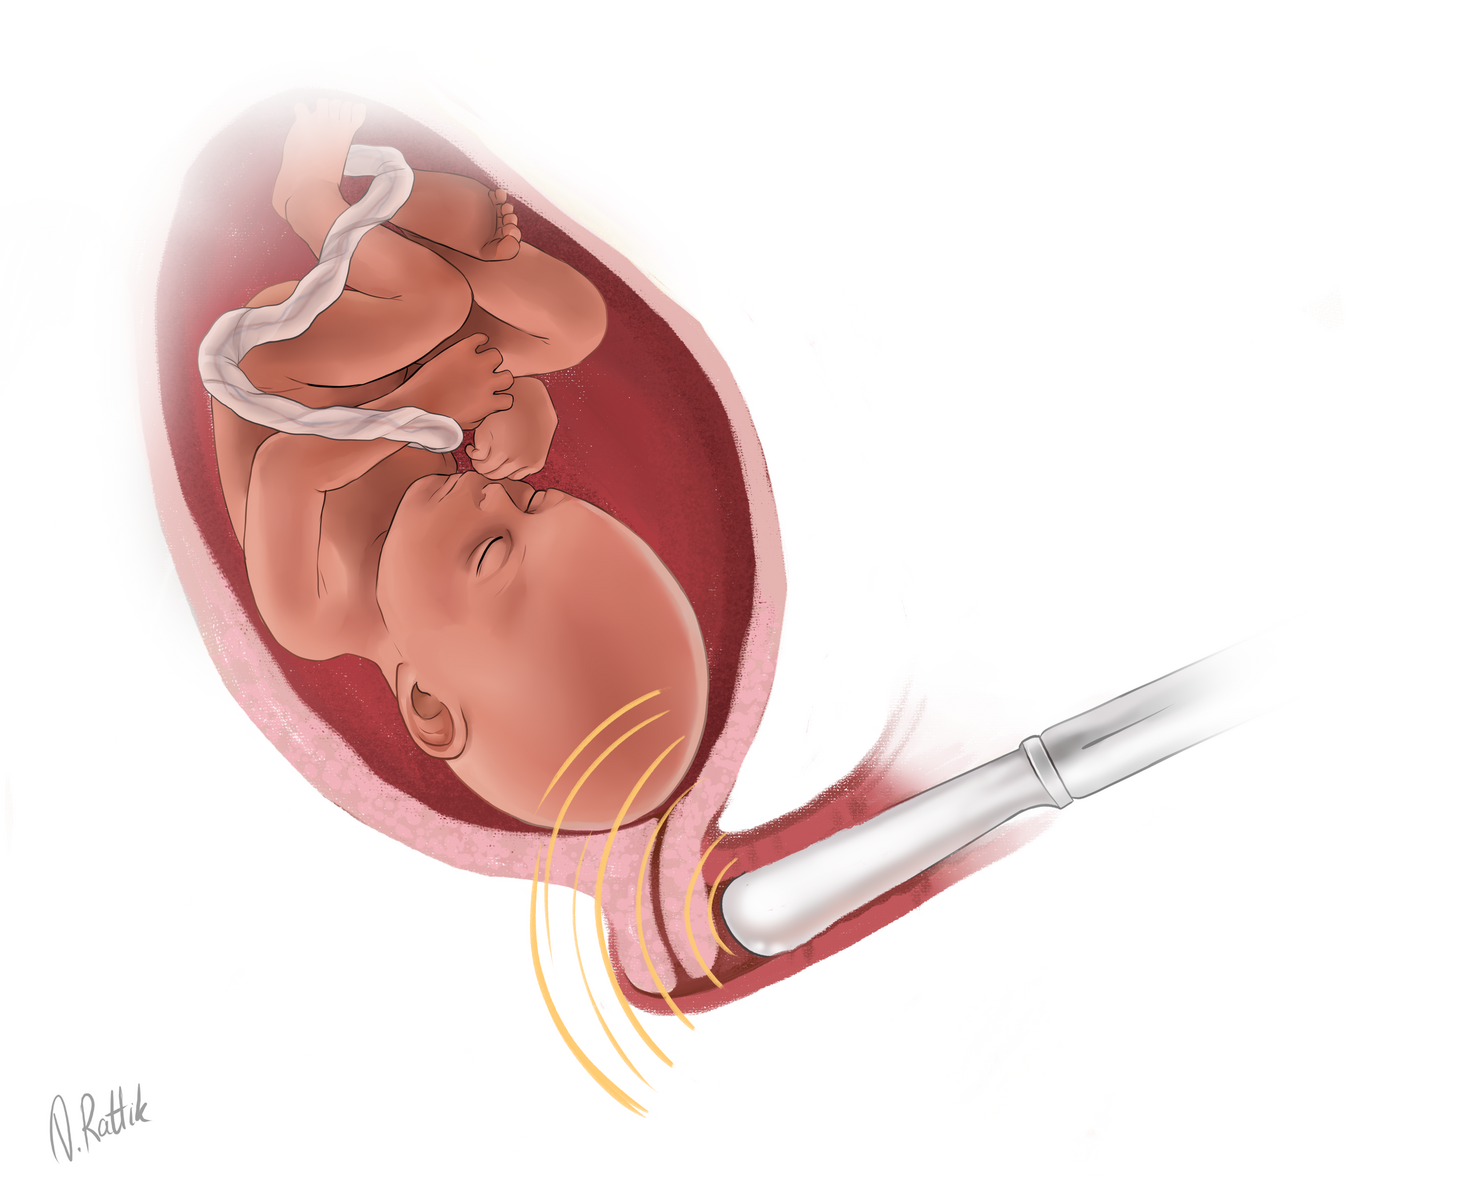

Околоплодный пузырь и плацента: структура и функции